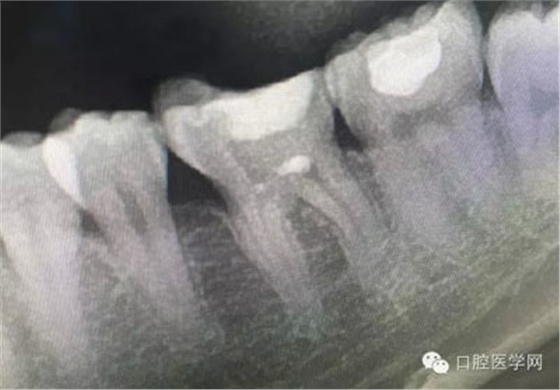

這是一例外院樹脂修復(fù)后十個(gè)月出現(xiàn)牙髓炎癥狀的患者。遇到這樣子的患者大家會(huì)怎么做,證明選擇,還有就是可做可不做治療的如何去平衡。

根管治療,我們?cè)诖髮W(xué)的時(shí)候就學(xué)習(xí)的東西,標(biāo)準(zhǔn)就在那里放著,可是很多時(shí)候我們熟視無(wú)睹,放任我們的想象去做。我們多些重視,多些心思,會(huì)好很多,認(rèn)真對(duì)待每顆牙齒。